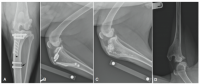

• Diagnostic Imaging

• Plain Radiography